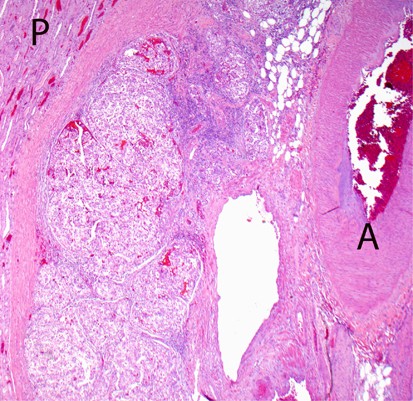

Figure 6

This shows intravenous tumor extending from sinus veins toward the parenchyma between renal pyramids (P). The accompanying artery (A) is present.